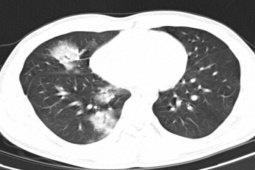

2 bệnh nhân nhập viện vì đau đầu âm ỉ, mệt mỏi, chán ăn, sút cân. Tại BV các bác sĩ chẩn đoán cả 2 người bị nang sán não. Điểm chung là cả 2 bệnh nhân này đều có thói...